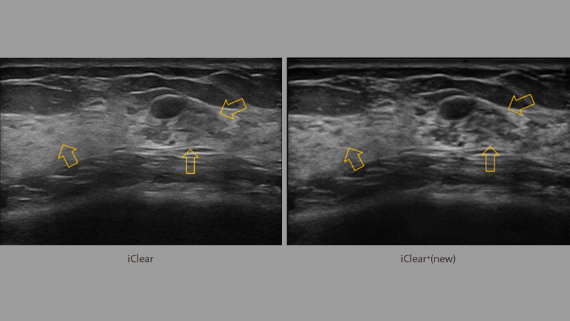

ImĂĄgenes clĂnicas